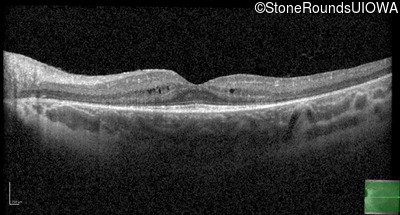

Age at visit: 8 years